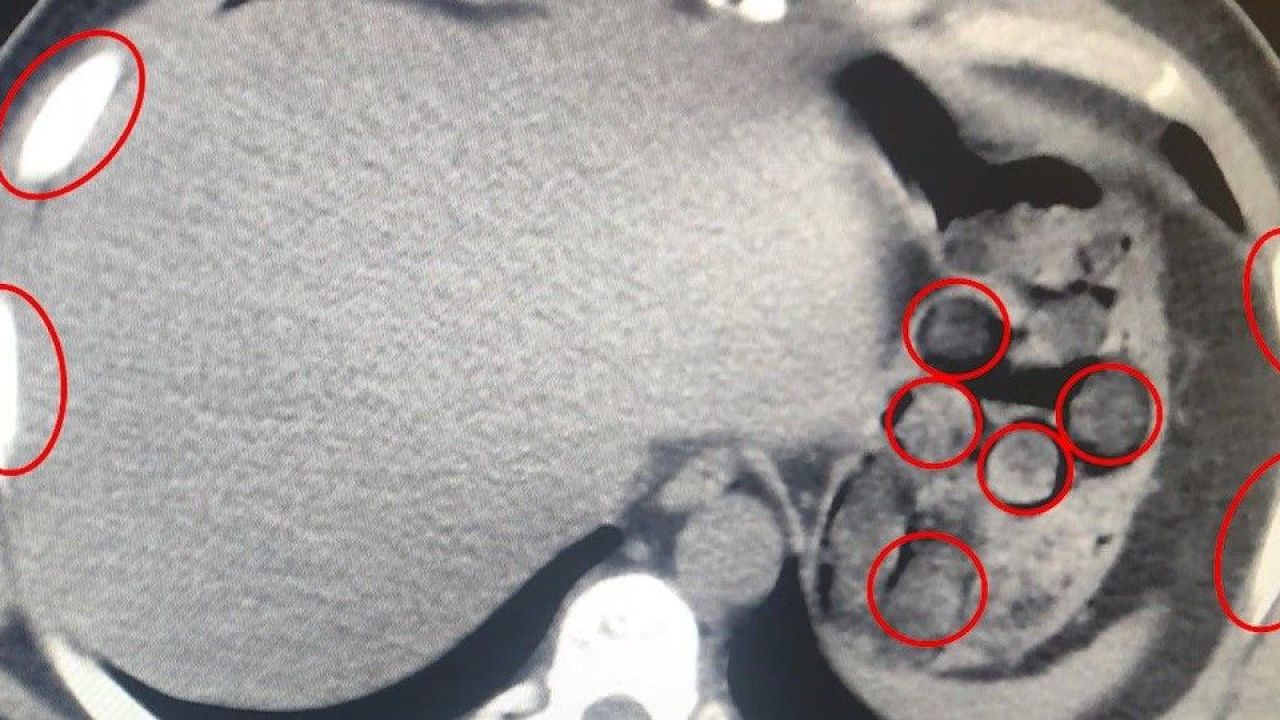

Bitlis İl Emniyet Müdürlüğü, uyuşturucu ile mücadele kapsamında gerçekleştirdiği operasyonda büyük bir sevkiyatı engelledi. Tatvan ilçesinde durdurulan bir yolcu otobüsünde seyahat eden yabancı uyruklu iki kişi, mideye gizledikleri 136 kapsül uyuşturucu maddeyle yakalandı.

1 Kilo 48 Gram Metamfetamin Tespit Edildi

Şüphelilerin sağlık kontrolleri sırasında yapılan tıbbi müdahalede, toplam 1 kilo 48 gram metamfetamin içeren 136 kapsülün yutularak taşındığı ortaya çıktı. Zanlılar, “Uyuşturucu Madde İmal ve Ticareti” suçlamasıyla gözaltına alındı. Emniyetteki işlemlerinin ardından çıkarıldıkları mahkemece tutuklanarak cezaevine gönderildi.